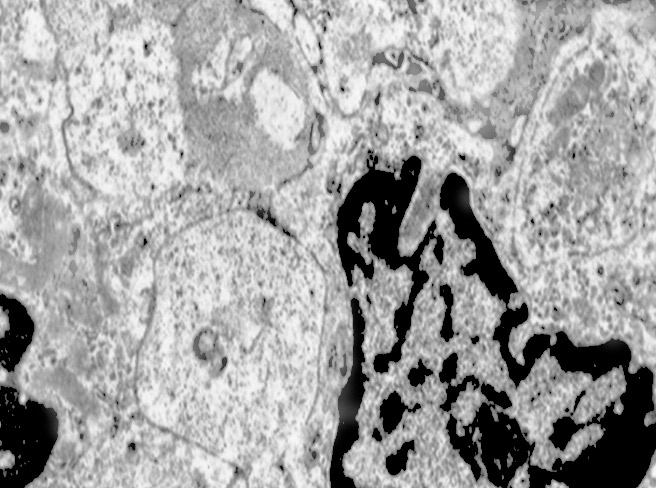

Alcune cellule meningoteliali sono sedi, sopratutto a livello delle fasce periferiche, di ampie vescicole, di forma irregolare le quali sono demarcate da una membrana a mono-strato; gli spazi di queste vescicole sono in buona parte occupati da materiale amorfo, da frammenti filamentosi e da organuli intracitoplasmatici,tutto sottoposto a degradazione.

E’ possibile anche il reperto di elementi cellulari aventi il citoplasma occupato da ampie vescicole,delimitate da una membrana a monostrato, le quali sono ricolme di materiale amorfo,da strutture granulo-filamentose o da frammenti di organuli.